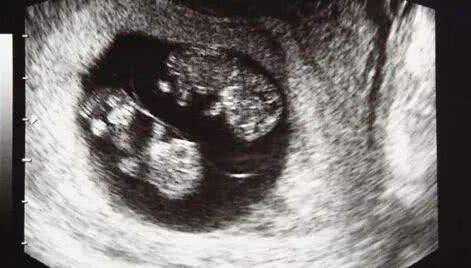

一段时间过后,在俩人身体状态差不多的时候又开始进入了备孕阶段,这一次两个人都很小心,第8周的时候去了医院做产检,这次的检查结果给小夫妻俩带来了惊喜,不仅怀孕,还是"双胞胎",一回家就迫不及待的把这个消息告诉了家人,开心的合不拢嘴。

但不幸的是又一次,到她怀孕第32周的时候,家人陪她来医院做检查,晴天霹雳一样的事情发生再次击垮了她,"又一次胎停了",这已经是她经历过的第三次胎停。况且这次怀的还是双胞胎,几乎接近崩溃边缘的她不敢相信,又做了一次彩超,但结果都是一样,确实是胎停了。家里人知道后伤心欲绝:"上辈子造了什么孽啊、真的要断子绝孙吗?"她听到更是难过了